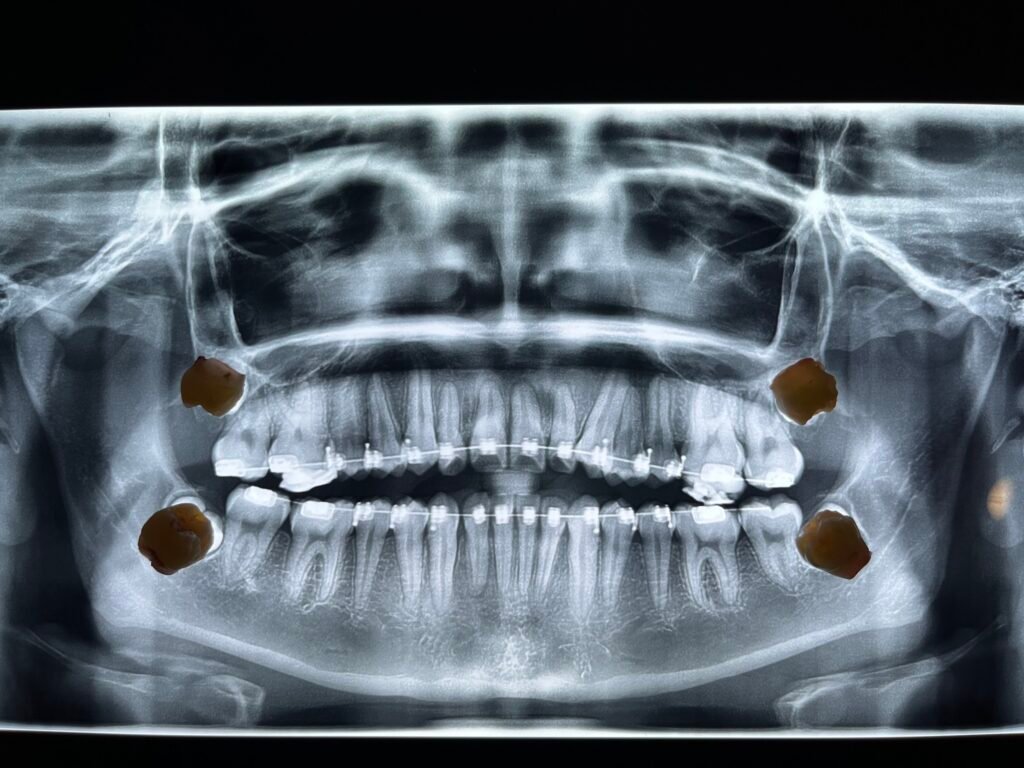

TERCEROS MOLARES (MUELAS DEL JUICIO)

Las muelas del juicio, también conocidas como terceros molares, son las últimas piezas dentales en aparecer. Suelen erupcionar entre los 17 y 25 años, y en muchos casos no tienen el espacio suficiente para salir correctamente, lo que puede causar molestias o problemas más serios.

Por estas razones, es fundamental realizar una evaluación radiográfica y un diagnóstico oportuno.

Evaluación completa con radiografías